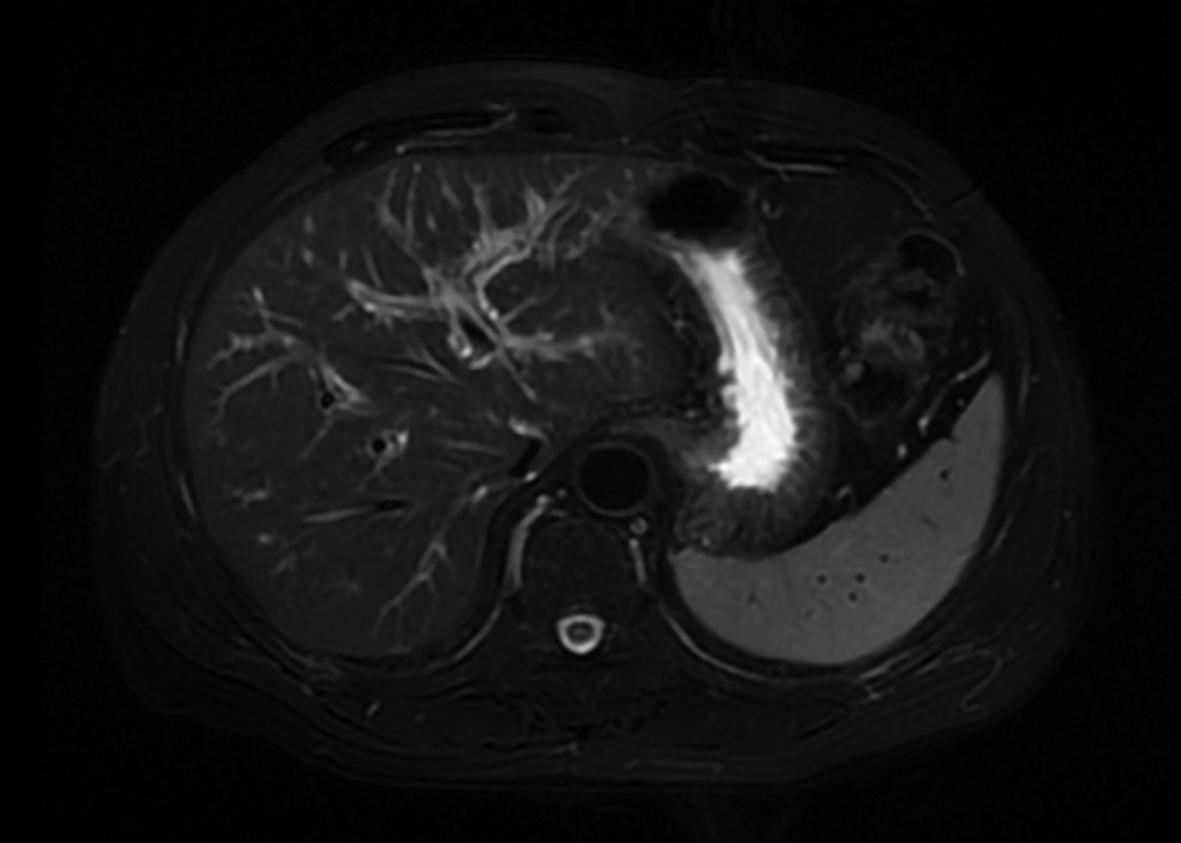

局部栓塞联合靶向免疫综合治疗肝肉瘤样癌1例报告

摘要(1328) HTML (453) PDF (3487KB)(83)

摘要: